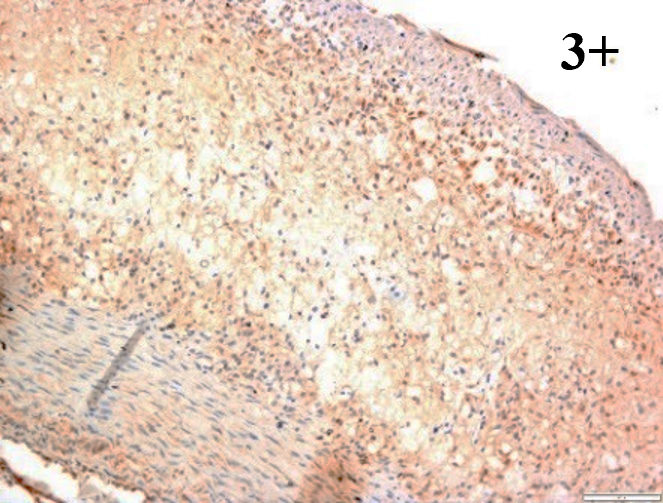

Immunoreactions of ICAM-1, VCAM-1, e-selectin, IL-6, IL-8, NF-

According to the percentage endothelial staining of cells, semi-quantitative

scores were applied. Score: 0 (negative); 1+ (1–10% positive cells); 2+

(11–25% positive cells) and 3+ (

Medium to high expressions of adhesion molecules, such as ICAM-1, VCAM-1 and

e-selectin were observed in the aortas of rabbits fed with HCD. This represents

the initiation of the lesion stage, where the endothelial cells have been

stimulated by the ox-LDL to express the adhesion molecules, which could lead to

the recruitment of monocytes and transmigrate into the intima by diapedesis as

well as differentiate into pro-atherogenic macrophages [47]. An increased

expression of pro-inflammatory biomarkers, such as IL-6, IL-8 and NF-